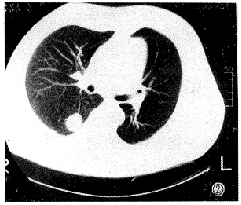

放射学实践990231 男性患者,50岁。因咳嗽3周伴脓痰1周入院。咳嗽呈阵发性,伴大量脓痰,并有胸痛、气喘、胸闷等。在当地医院抗炎无好转,脓痰转为白粘痰。入院体检及心电图、B超、肺功能检查均无异常。胸片见右肺门区一圆形高密度影(图1)。CT见病灶位于右下叶背段,大小约2cm×2cm,密度均匀,边缘光滑锐利、似有分叶,肺窗见单支血管供血(图2)。MRI见肿块呈等T1、等T2信号,肺门、纵隔未见肿大淋巴结(图3)。诊断:右下叶背段肿瘤性病变。

图2 胸部CT肺窗:右肺下叶背段肿块。